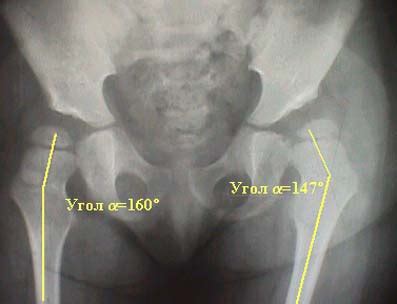

Рентгенанатомия

Справочные материалы Возрастные и половые показ...

Шеечно диафизарный угол тазобедренного сустава